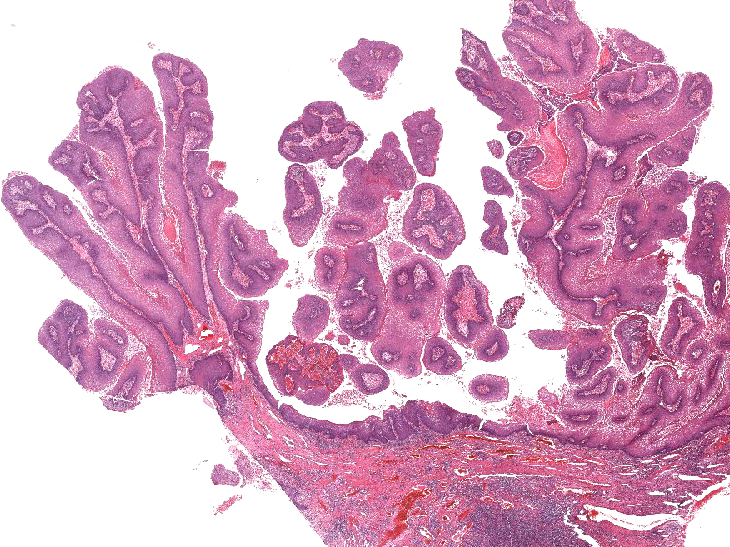

Microscopic (histologic) description

- Resembles condyloma acuminatum

- Diagnostic criteria

- Well formed papillae with a prominent central fibrovascular core

- Hyperkeratosis with parakeratosis and marked acanthosis

- Koilocytes on upper third of the squamous epithelium

- Chronic inflammatory infiltration

- Local extension and displacement of surrounding tissues but no evidence of dysplasia / invasion (WHO Classification of Tumours Editorial Board: Digestive System Tumours, 5th Edition, 2019)

- Low mitotic rate, usually confined to the basal layer with no abnormal mitoses (Histopathology 2017;70:938)

- About 30 - 35% may develop an invasive component; especially in high risk HPV positive cases (Virchows Arch 2020;476:543, Dis Colon Rectum 1989;32:481)

Microscopic (histologic) images